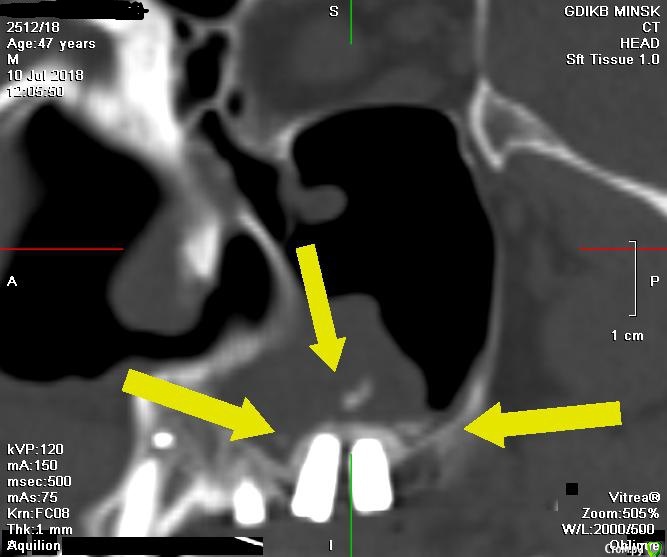

V20 Опубликовано 28 апреля, 2019 Поделиться Опубликовано 28 апреля, 2019 (изменено) Доброго времени суток , помогите пожалуйста разобраться с ситуацией.В мае 2018 года был проведен синус лифтинг с одновременной установкой 3 имплантов, Спустя 5-7 дней на фоне приема антибиотиков(Аугментин), развился левосторонний гайморит. Прошел курс консервативного лечения, пазуха успокоилась.Было решено протезироваться . В феврале 2019 года при откручивании ФД выкрутился имплант (по центру ) и образовался свищ, . Была сделана пластика свища. Сообщение закрылось.На настоящий момент сохраняется чуть заметная припухлость щеки в проекции пазухи и немного поднывает десна.(больше в районе крайнего импланта) На ощупь языком в месте соприкосновения десны и щеки небольшая припухлость ( похоже по проекции разреза).Что интересно с утра десна не болит начинается дискомфорт чуть позже. Уважаемые доктора , помогите пожалуйста в дальнейшей тактике - мнения врачей кардинально расходятся(снимки через неделю после синус лифтинга Снимок 3 месяца назад после консервативного лечения у ЛОРа Последний снимок (2 месяца назад) И еще хотелось бы услышать Ваше мнение о импланте на месте 24 зуба Заранее спасибо. Изменено 28 апреля, 2019 пользователем V20 Ссылка на комментарий

Bier Опубликовано 1 мая, 2019 Поделиться Опубликовано 1 мая, 2019 Я бы раскрыл как при синуслифтинге, чтобы оценить что там такое. По КТ все не очень хорошо. Ссылка на комментарий

V20 Опубликовано 1 мая, 2019 Автор Поделиться Опубликовано 1 мая, 2019 (изменено) Я бы раскрыл как при синуслифтинге, чтобы оценить что там такое. По КТ все не очень хорошо.Доктор, не могли бы вы уточнить что именно нехорошо, просто лечащие стоматологи говорят что кроме синусита все норма... Изменено 1 мая, 2019 пользователем V20 Ссылка на комментарий

Bier Опубликовано 1 мая, 2019 Поделиться Опубликовано 1 мая, 2019 синусит и есть не хорошо. У него есть причина. 1 Ссылка на комментарий